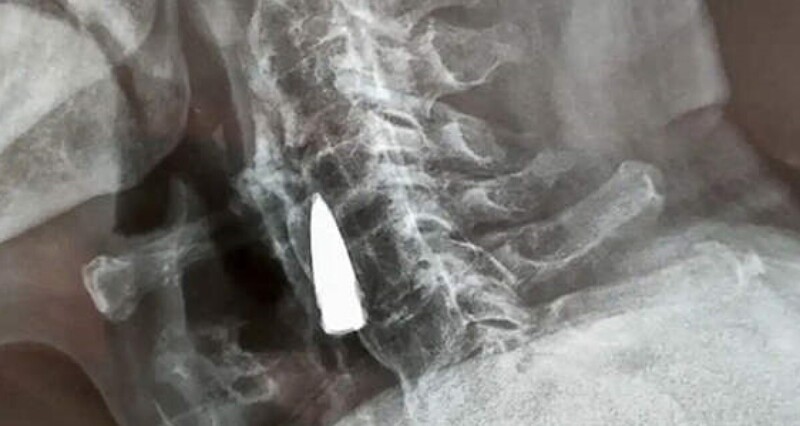

Після падіння з балкона свого будинку в китайській провінції Шаньдун, Чжао Хе, гніваючи на свій поважний вік, почував себе нормально - по принаймні, як кажуть його рідні, він не повідомляв їм про будь-які симптоми. Болю він не відчував, але через деякий час у ветерана Другої світової війни з'явився легкий дискомфорт у шиї. Син вирішив відвезти його до лікарні на обстеження. Почувши про його падіння, лікарі порекомендували зробити рентген, щоб переконатися, що він не отримав серйозні пошкодження шиї. Однак замість перелому рентген виявив у шиї у чоловіки сторонній предмет, який пізніше ідентифікували як стару кулю.

Сам Чжао вважає, що куля перебувала у його шиї з 1944 року. Очевидно, вона справді потрапила до нього переході через річку. Куля пройшла через ліву частину носа, пробила йому верхню щелепу та вибила кілька зубів, після чого застрягла у шиї. Втім, це лише його здогад.

Вивчивши рентгенівські знімки, лікарі сказали Чжао Хе та його родині, що куля пройшла поряд з деякими великими кровоносними судинами і що, оскільки вона не викликала у нього жодних проблем, краще залишити її, як є. Ветеран війни погодився. «Я був здоровий усі ці роки, тому зараз немає причин щось міняти», - сказав Чжао Хе.